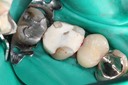

Mark Chun #14 caries removal